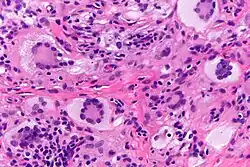

Las células gigantes de Touton, siendo células gigantes multinucleadas, puede ser distinguidas por la presencia de varios núcleos en un patrón distintivo. Contienen un anillo de núcleos que rodean un citoplasma homogéneo central, mientras que el citoplasma que rodea a los núcleos es espumoso.[4][5] El citoplasma rodeado por los núcleos ha sido descritos como anfófilo y eosinofílico, mientras que el citoplasma de la periferia celular tiene un aspecto pálido y espumoso.[6]